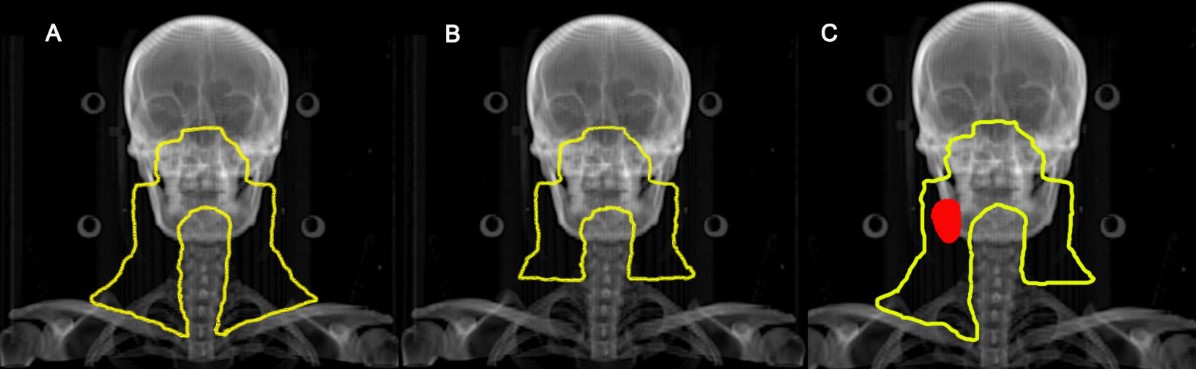

鼻咽癌预防照射范围示意图

A:对照组:无论有无淋巴结转移均行全颈部预防照射

B:试验组:无颈部淋巴结转移,双侧颈部行上半颈部照射

C:试验组:单侧淋巴结转移(红色区域),淋巴结阴性侧行上半颈部照射